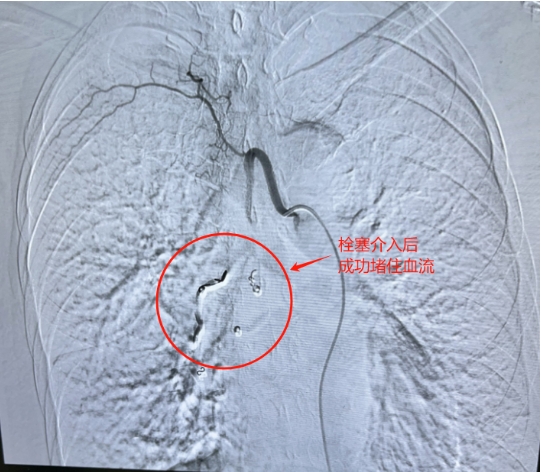

在和阿姨的家人详细沟通,征得他们同意后,医生们迅速为阿姨完善了各项检查,并马上进行了急诊手术。手术中,医生们全神贯注,精准操作,成功完成了经导管选择性支气管动脉栓塞治疗。

蒋秀清主任团队行经导管选择性支气管动脉栓塞治疗

幸运的是,手术非常成功!术后,阿姨的血很快就止住了,病情也逐渐稳定下来,目前正在慢慢康复中。